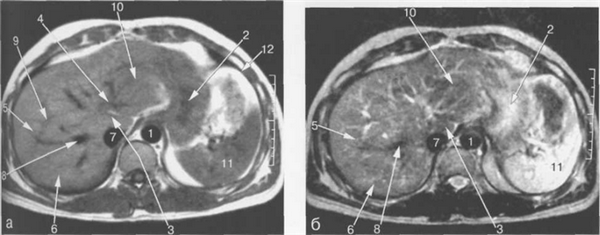

Паренхима печени имеет короткое время релаксации на Т1- и Т2-ВИ. На Т1-ВИ неизмененная печеночная ткань характеризуется средней интенсивностью сигнала, схожей с таковой поджелудочной железы, но более высокой интенсивностью по сравнению с сигналом коркового вещества почек, селезенки и мышц.

На Т2-ВИ паренхима печени характеризуется низкой интенсивностью сигнала, которая соответствует таковой мышц, схожей или более низкой по сравнению с интенсивностью сигнала поджелудочной железы, и значительно более низкой интенсивностью сигнала по сравнению с селезенкой и почками (рис. 11.14—11.16). На Т1- и Т2-ВИ печень имеет однородную структуру.

Интенсивность сигнала сосудов печени зависит от скорости кровотока и от того, какая импульсная последовательность использовалась. На SE-импульсных последовательностях без внутривенного контрастирования печеночные сосуды видны как образования с низкой интенсивностью сигнала либо как зоны, не дающие сигнала. На градиентных импульсных последовательностях сосуды характеризуются высокой интенсивностью сигнала по сравнению с печеночной паренхимой, что в некоторых случаях позволяет выявлять внутрисосудистые образования или тромбы.

Рис. 11.14. МРТ брюшной полости на уровне ворот селезенки.

1 — аорта; 2 — нижняя полая вена; 3 — левая желудочная артерия; 4 — селезеночная артерия; 5 — желудок; 6 — селезенка; 7 — толстая кишка; 8 — хвост поджелудочной железы.

Рис. 11.15. МРТ брюшной полости в аксиальной плоскости на уровне желчного пузыря.

1 — аорта; 2 — нижняя полая вена; 3 — селезеночная вена; 4 — верхняя брыжеечная артерия; 5 — желчный пузырь; 6 — левый надпочечник; 7 — правый надпочечник; 8 — левая почка; 9 — кортикальный слой левой почки.

Рис. 11.16. MPT брюшной полости в аксиальной плоскости на уровне головки поджелудочной железы.

1 — аорта; 2 — нижняя полая вена; 3 — верхняя брыжеечная артерия; 4 — верхняя брыжеечная вена; 5 -головка поджелудочной железы; 6 — верхний полюс правой почки; 7 — левая почка; 8 — левая почечная артерия; 9 — общий желчный проток.